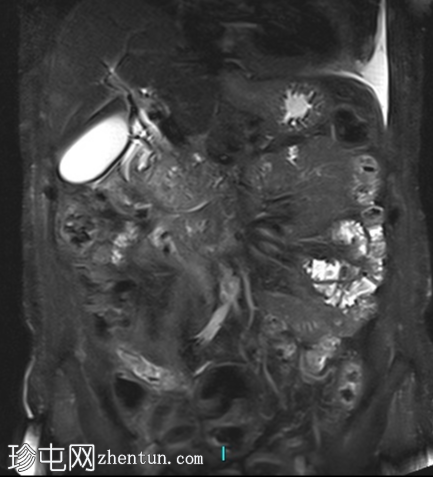

冠状位T2加权像

脂肪抑制像

2.png

胰腺钩突附近可见边界不清的肿块,T2加权像呈不均匀中等信号,弥散受限明显。肿块大小为4.1 x 5 x 3 cm(前后径 x 横径 x 头尾径)。伴有胰管扩张,直径约6 mm。

肝脏可见多个大小不一的可疑病灶(从亚厘米级到2厘米不等)。T2加权像呈高信号,弥散受限明显。

远端胆总管突然变窄,但未完全阻塞。

胰腺周围可见多发囊性病变,部分与主胰管相连,提示胰腺导管内乳头状黏液性肿瘤(IPMN)。

双侧胸腔积液,左侧较多。